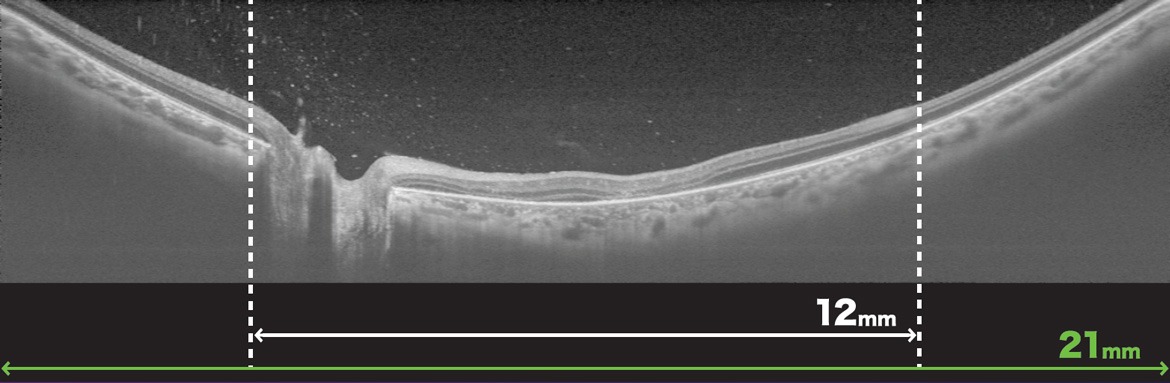

- Wide-Field OCT 최대 21mm Scan

12×9mm Wide Scan은 시신경과 황반을 모두 포함하며, 한 번의 촬영으로 Posterior pole 전체에 대한 종합적인 평가를 제공합니다.